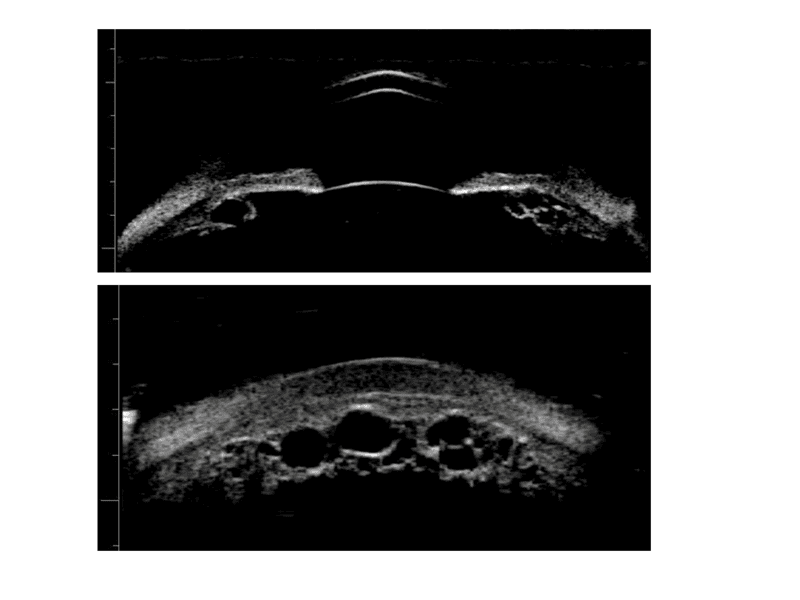

La biomicroscopie ultrasonore est la méthode de choix pour examiner le corps ciliaire et caractériser un syndrome d’iris plateau.2,3 Les principales caractéristiques échographiques d’un syndrome d’iris plateau sont (Figure 1) :

- Un corps ciliaire volumineux (notamment des procès volumineux)

- Une antéroposition du corps ciliaire

- Un effacement partiel ou complet du sulcus ciliaire

- Une profondeur de chambre antérieure normale ou légèrement diminuée

- Une distance corps ciliaire-trabéculum très diminuée

Figure 1. Biomicroscopie ultrasonore (Aviso 50 MHz, Quantel, France).